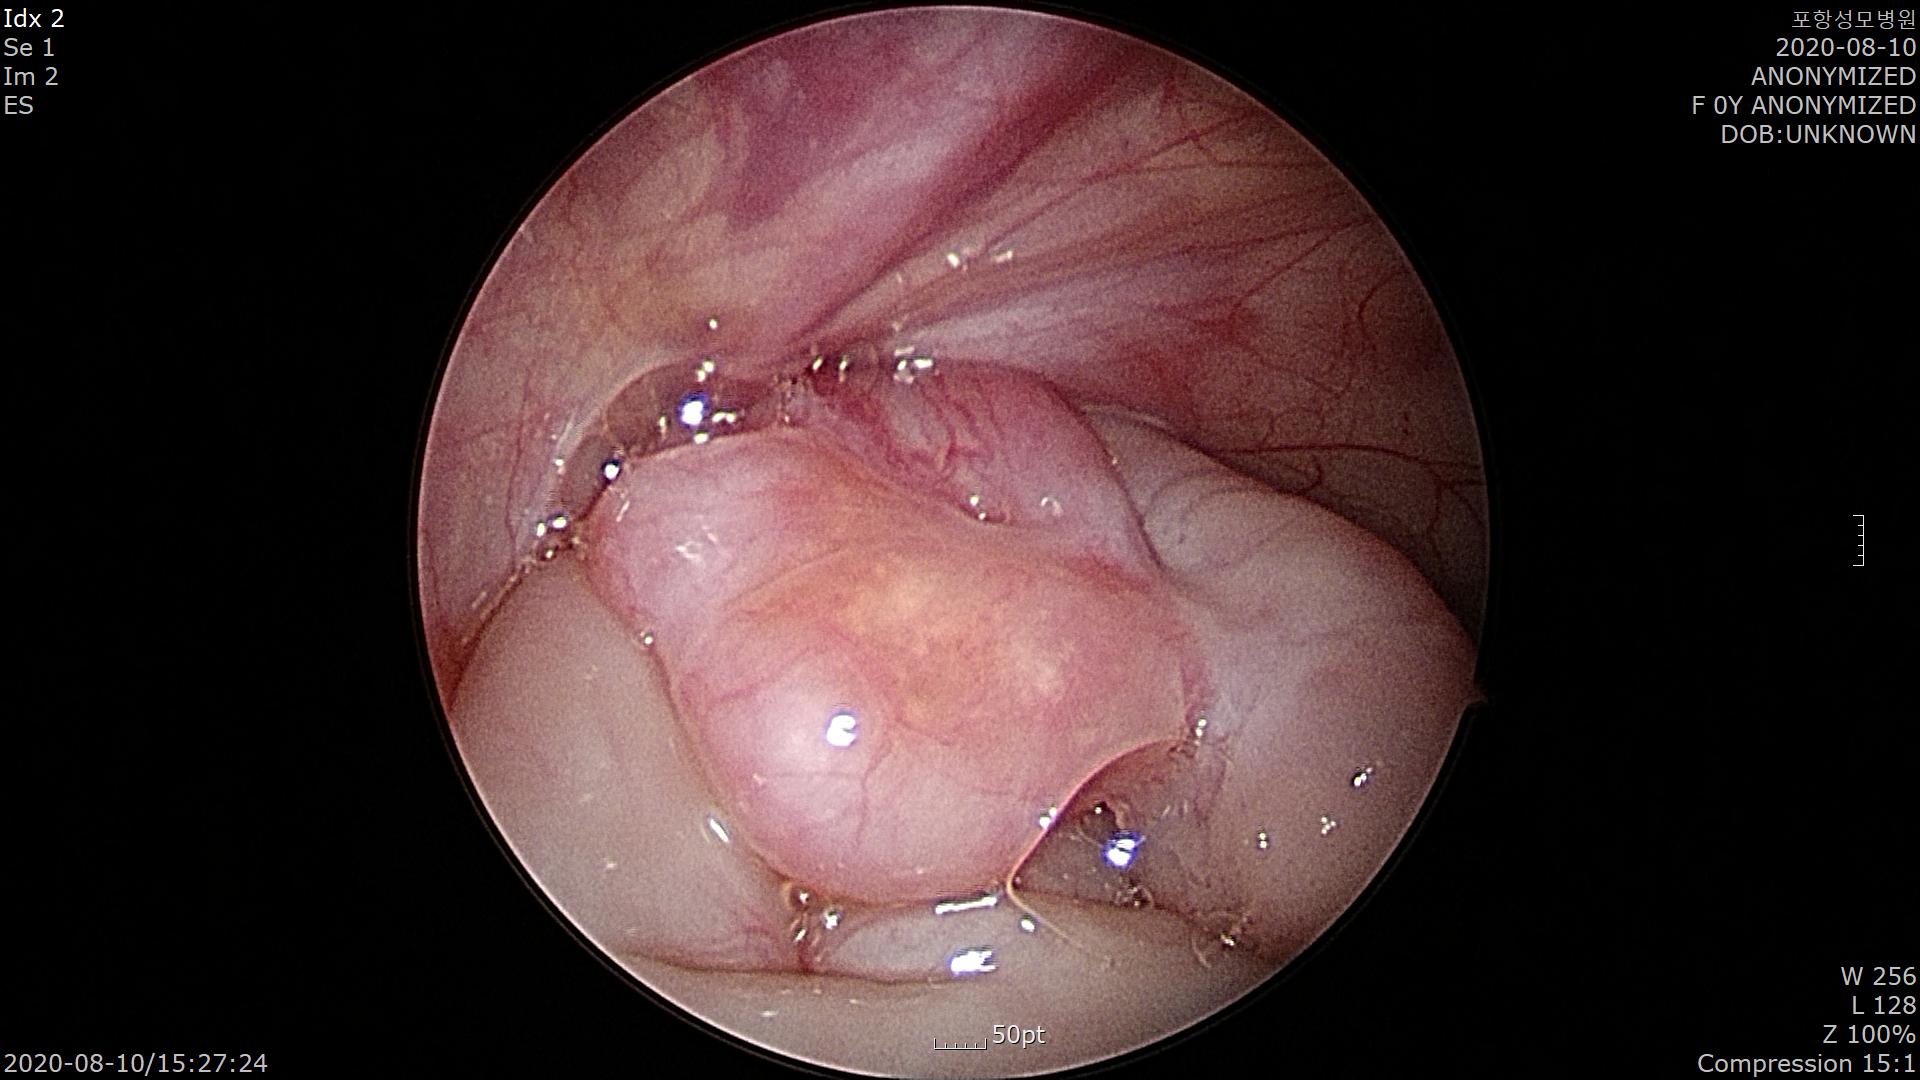

우측 서혜부 탈장이 보이고 우측 난소가 탈장구멍에 감돈되어 있습니다.

조심스럽게 감돈된 우측 난소를 탈장구멍에서 빼냅니다.